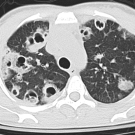

A 39-year-old woman presented to the emergency department with generalized weakness, fevers, and a productive cough over the past 3 days. Her medical history was significant for intravenous drug use, MRSA...

02/11/2020